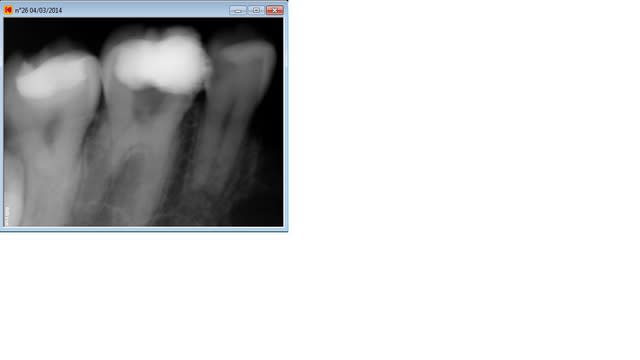

Ce qui merde à mon avis ce sont tes hero shapers ( ca doit tasser de la m.. au fond), passes au réciproc. Pour te frustrer un peu plus ci dessous des radios d'endos réalisées sans cathétérisme manuel et oh ! sacrilège au monocone scellé, 10 mn par canal , sans se casser le tronc.-))

Je vois que tu a le système KODAK comme moi, clic droit sur la radio

Clic droit sur la radio, envoyer vers dossier, choisir dans le menu déroulant format Jpeg, envoyer.

R1 nt0dqo - Eugenol

R3 zt7ydp - Eugenol

R2 pu48rd - Eugenol

R4 idqien - Eugenol